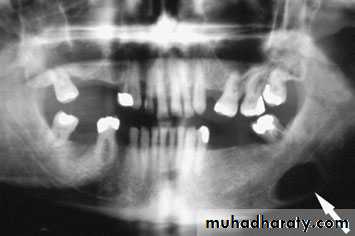

80% of sialoadenitis occur in sub mandibular salivary gland?80% is radio opaque stone.

Acute left submandibular sialadenitis.